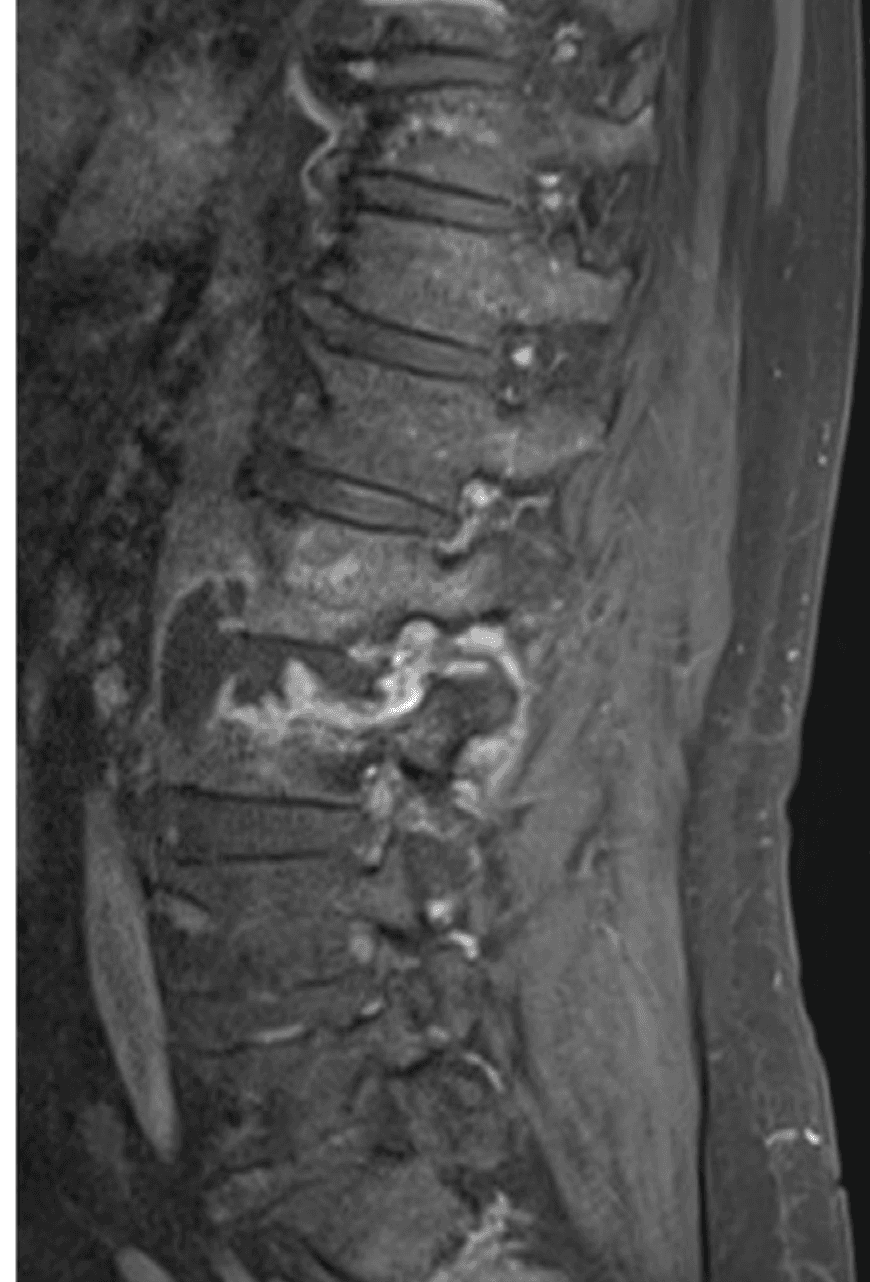

Hemoglobin is 10.8 g/dL, erythrocyte sedimentation rate 86 mm/hour, and C-reactive protein 11.4 mg/dL. MRI shows L2-L3 discitis and osteomyelitis with an adjacent paravertebral abscess. CT-guided biopsy shows necrotizing granulomatous inflammation. Routine cultures remain sterile, and mycobacterial studies are sent from the biopsy specimen.

Lumbar spine MRI showing destructive changes centered at L2-L3 with an adjacent paravertebral fluid collection.